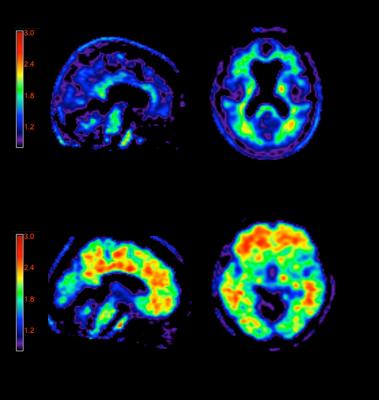

A negative Amyvid scan indicates sparse to no neuritic plaques and is inconsistent with a neuropathological diagnosis of AD at the time of image acquisition; a negative scan result reduces the likelihood that a patient's cognitive impairment is due to AD. A positive Amyvid scan indicates moderate to frequent amyloid neuritic plaques; neuropathological examination has shown this amount of amyloid neuritic plaque is present in patients with AD, but may also be present in patients with other types of neurologic conditions as well as older people with normal cognition.[9]

Amyvid is a radioactive diagnostic agent that is injected into the bloodstream, where it crosses the blood-brain barrier and selectively binds to amyloid plaques. The fluorine 18 (F 18) isotope produces a positron signal, which is detected by a PET scanner.[9],[10] Physicians who read Amyvid PET scans should complete a comprehensive training program available through live events or online at AmyvidTraining.com.[9]

A negative Amyvid scan indicates sparse to no neuritic plaques and is inconsistent with a neuropathological diagnosis of AD at the time of image acquisition; a negative scan result reduces the likelihood that a patient's cognitive impairment is due to AD. A positive Amyvid scan indicates moderate to frequent amyloid neuritic plaques; neuropathological examination has shown this amount of amyloid neuritic plaque is present in patients with AD, but may also be present in patients with other types of neurologic conditions as well as older people with normal cognition. Amyvid is an adjunct to other diagnostic evaluations.